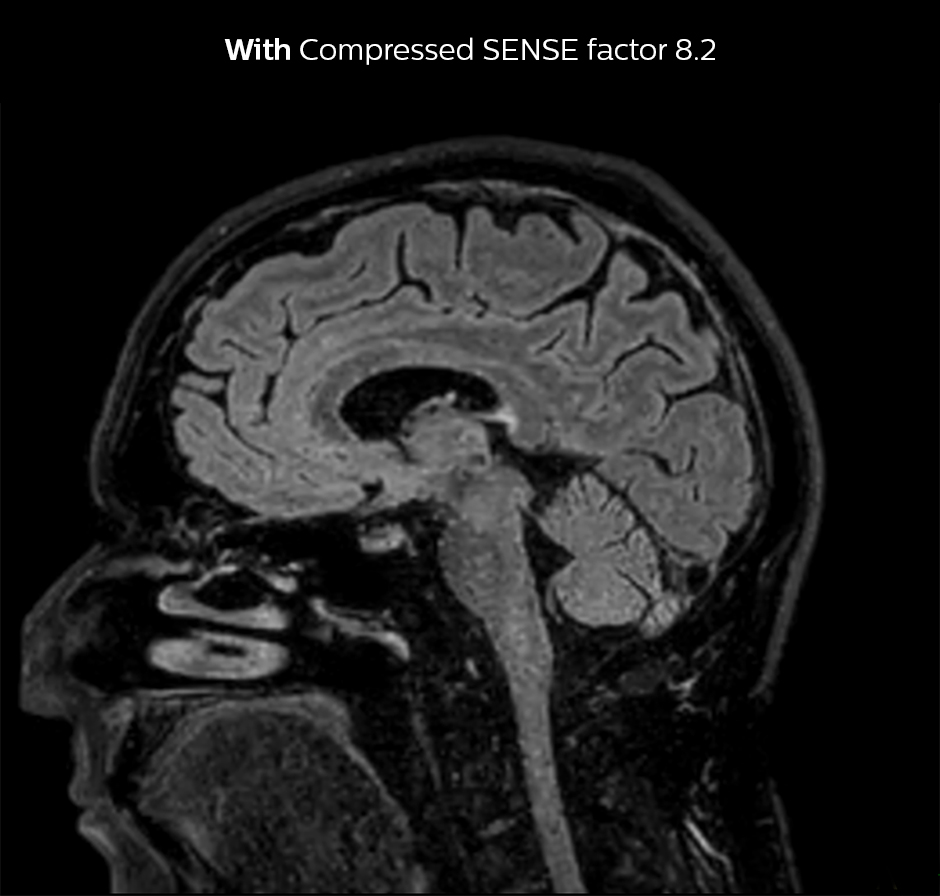

Dr. Sartoretti remembers how Compressed SENSE immediately impressed her in the first scans. “Our first sequence with Compressed SENSE was a 3D FLAIR in the brain on the Ingenia 1.5T, where we used a Compressed SENSE factor of 8.2. Then we tried a 3D TSE mDIXON post-contrast sequence with a CS factor of 7. In both cases the quality was really good.”

Compressed SENSE allows 28% shorter scan time with the same spatial resolution.

3D FLAIR, scan time 5:02 min, voxel size 1.1 x 1.1 x 1.1 mm, Ingenia 1.5T.

3D FLAIR, scan time 3:36 min, voxel size 1.1 x 1.1 x 1.1 mm, Ingenia 1.5T.